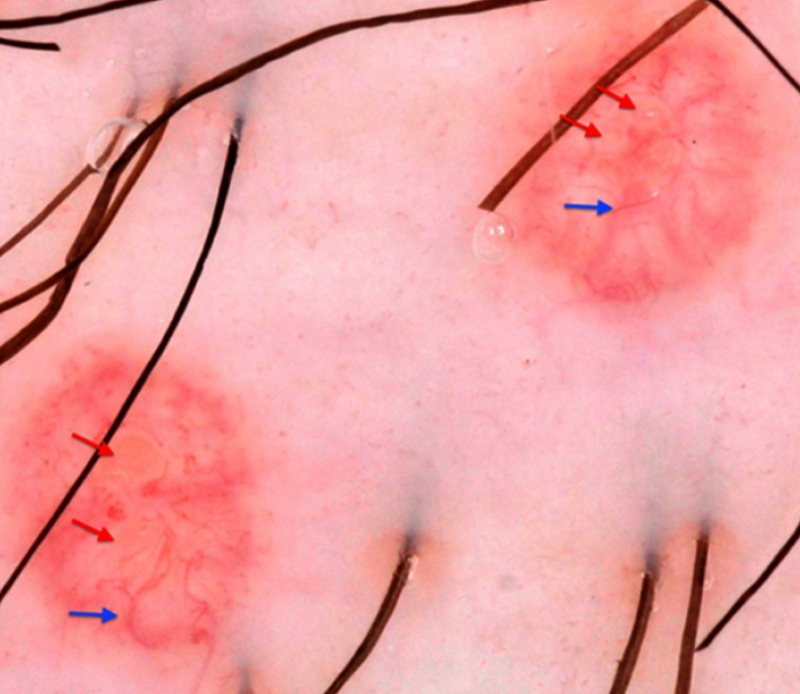

A dermatoscopia pode facilitar o diagnóstico ao revelar uma área central, polilobular, branco-amarelada, sem estrutura, circundada por vasos em padrão de coroa.[13][Figure caption and citation for the preceding image starts]: Achados dermatoscópicos do molusco contagioso. As setas vermelhas indicam estruturas polilobulares brancas a amarelas; setas azuis: vasos de coroa. (Dermoscopia com luz polarizada, ampliação original 10x)Clinical, Cosmetic and Investigational Dermatology 2019:12 373-381. Originalmente publicado por e usado com permissão de Dove Medical Press Ltd. [Citation ends].